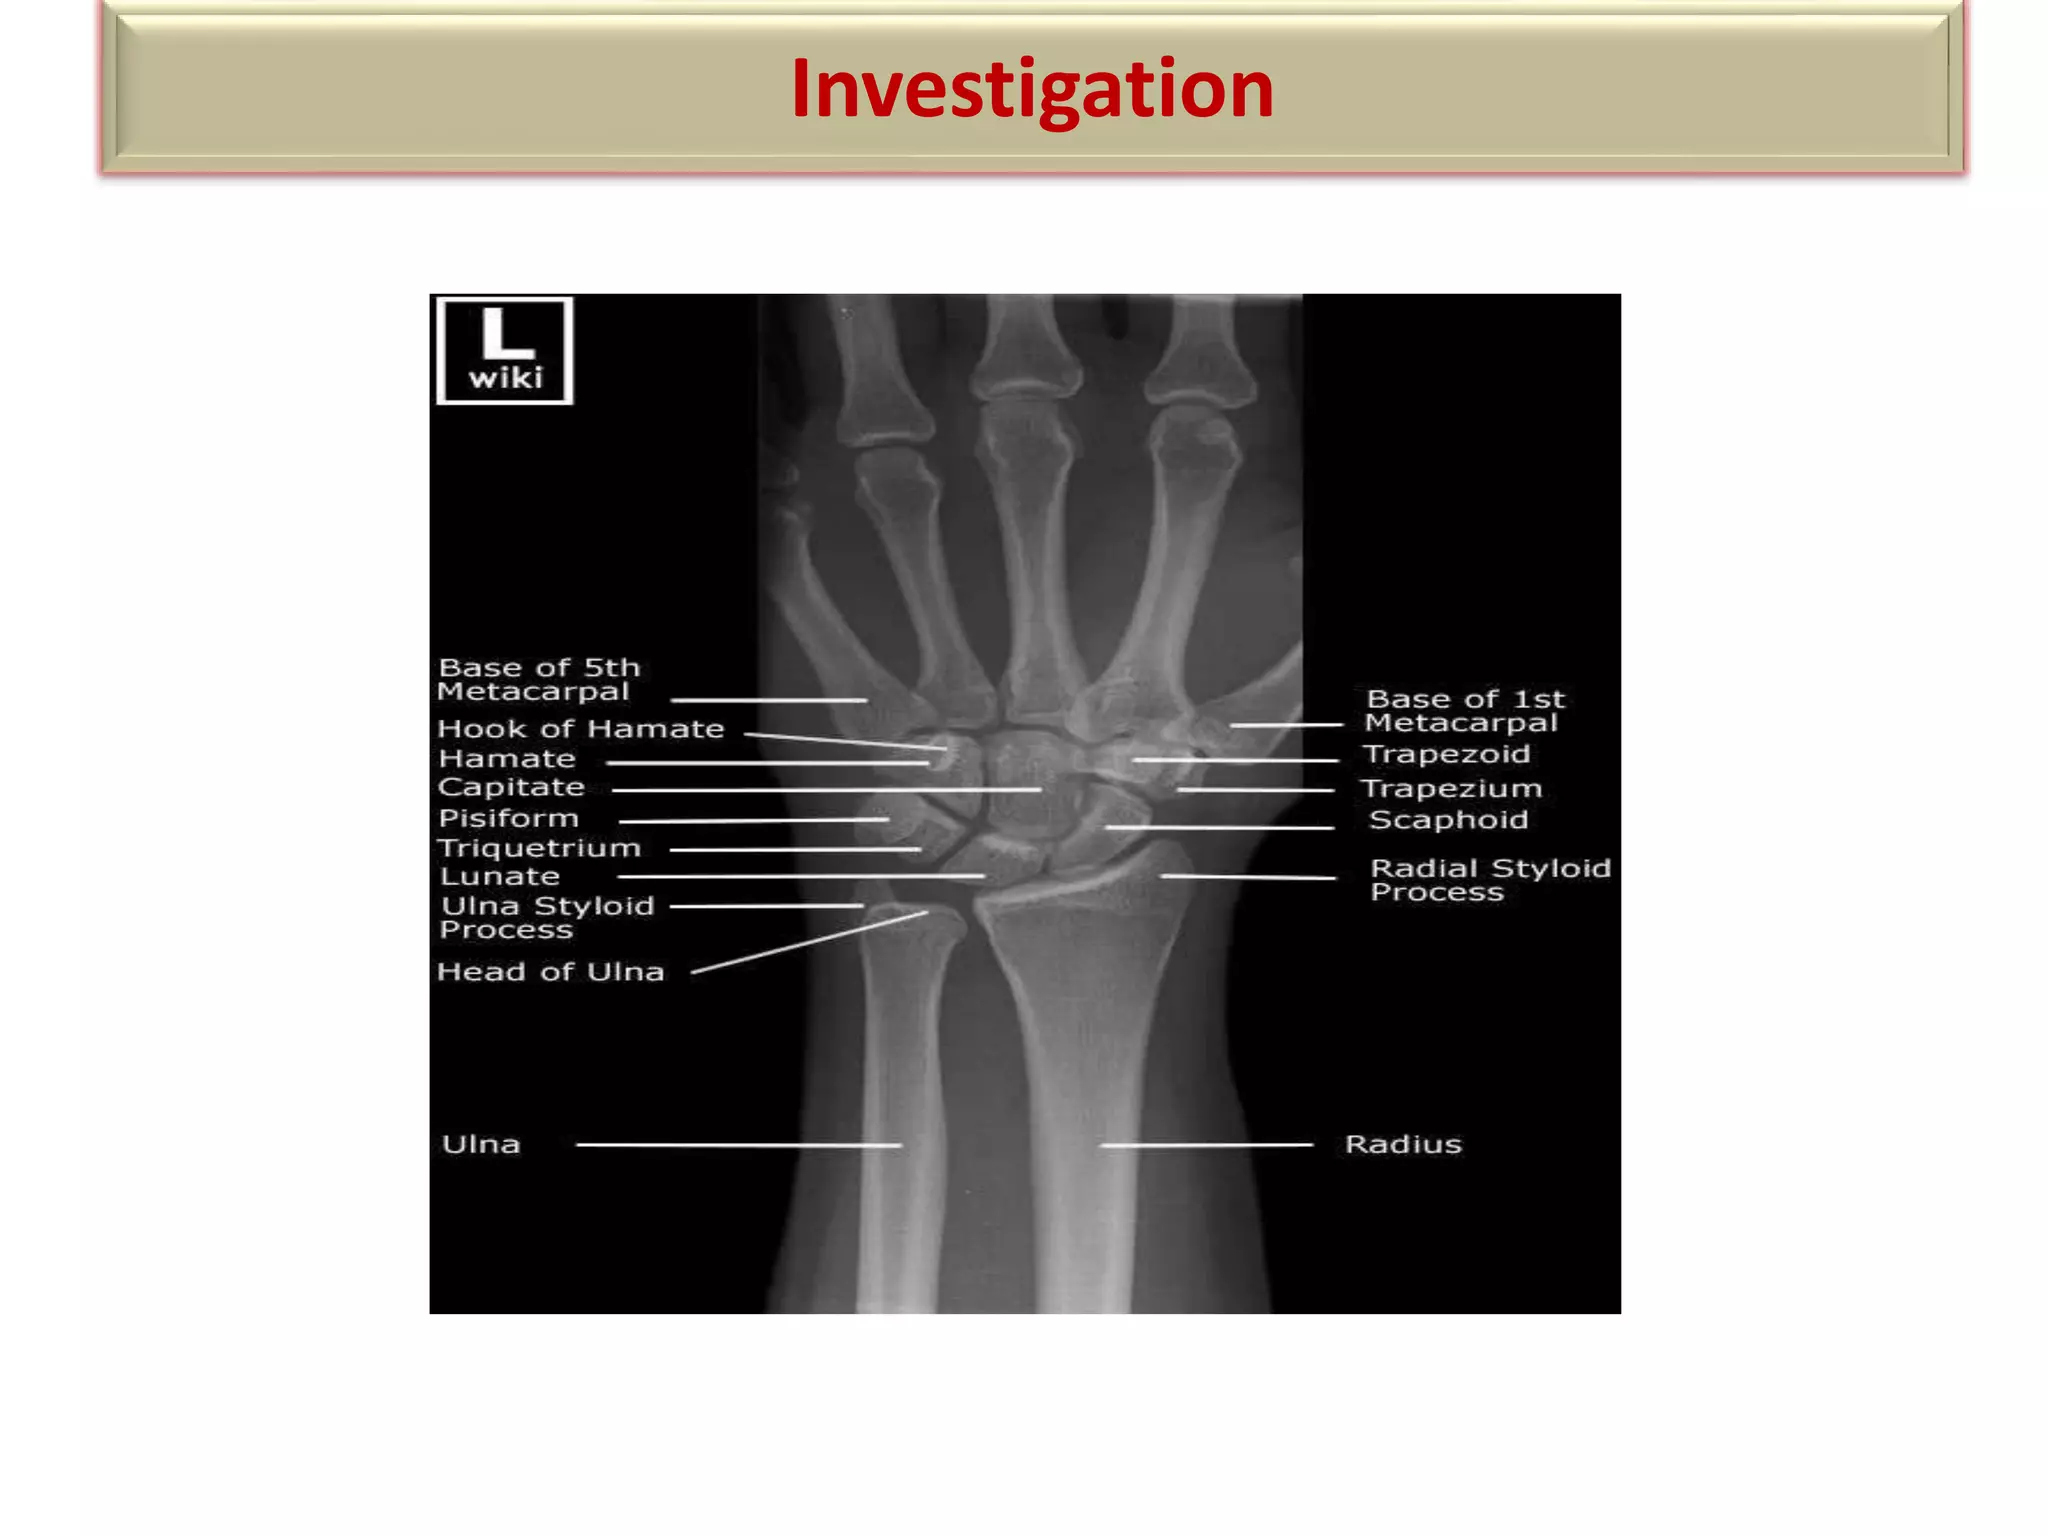

Wrist Bone Anatomy X Ray

Wrist Bone Anatomy X Ray mavink.com

Wrist Anatomy X Ray Labeled

Wrist Anatomy X Ray Labeled mavink.com